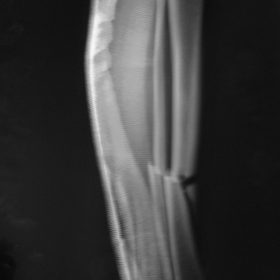

Τα κατάγματα της Διάφυσης των οστών της κνήμης και του Μηριαίου οστού στη σύγχρονη ΟΡΘΡΟΠΑΙΔΙΚΗ αντιμετωπίζονται με ΕΝΔΟΜΥΕΛΙΚΗ ΗΛΩΣΗ.

Δύο τομές 3 εκατοστών και 1 εκατοστού αντιστοίχως για την εισαγωγή και το κλείδωμα του ήλου μέσα στο οστό. Η μέθοδος είναι κλειστή,σχεδόν αναίμακτη,διάρκειας 60 λεπτών,με τη βοήθεια C-ARM (τηλεόρασης).